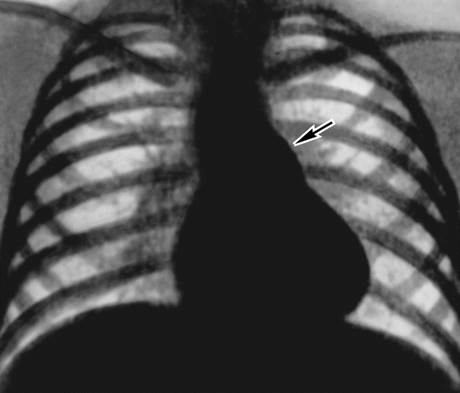

Для подтверждения диагноза назначают рентгенографию, которая позволяет увидеть изменения в легочной ткани и сосудистом пучке. Также проводятся УЗИ и эхокардиография, которые помогают выявить гипертрофию левого желудочка сердца и определить направление сброса крови.

- Рентгенография помогает оценить размер сердца и выявить повреждения легочной ткани.